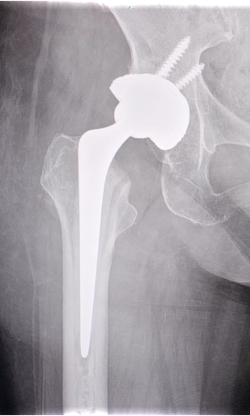

- Patient was planned for right total hip replacement, followed by left total hip replacement at a later stage

Intraoperative

- Intraoperatively, the bone was noted to be fragile

- Extra care had to be taken to avoid intraoperative iatrogenic fracture

- Right total hip replacement was done successfully